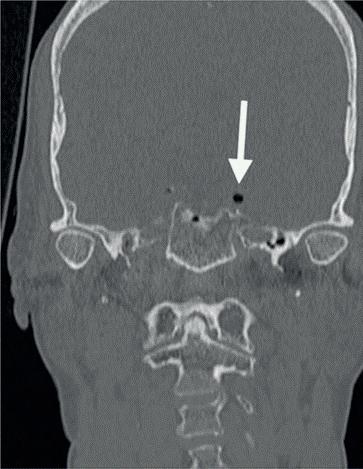

In dit geval heb ik mijn collega die belde voor advies, geadviseerd om contact op te nemen met de implantoloog waar ze mee samenwerkt. De kans dat implantologie op termijn nodig zal zijn, is namelijk heel erg groot. De patiënt kon dezelfde dag nog terecht bij tandarts-implantoloog Tristan Staas. Naast de aanwezige solo is er een CBCT gemaakt (foto 5 en 6). De behandelmogelijkheden zijn hierna uitgebreid besproken.

Er is in deze casus door de implantoloog gekozen om element 21 terug te plaatsen, in de hoop dat het zo lang mogelijk goed blijft gaan. Het stolsel is met een implantaatboor uit de alveole verwijderd en de alveole is iets verruimd. Eigenlijk dezelfde procedure als bij een autotransplantatie. Hierna is het element uitgebreid afgespoeld met fysiologisch zout, teruggeplaatst en aan de spalk bevestigd. Voorheen was,

5. Solo gemaakt meteen na het trauma door de spoeddienst.

6. Screenshot van de CBCT.